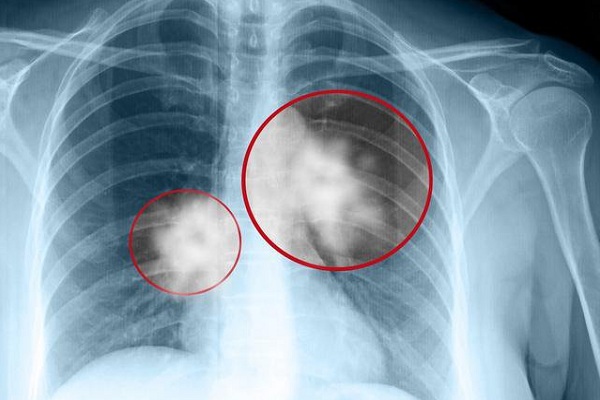

女性吸烟者的数码胸部x光片显示肺癌

肺癌的线表现